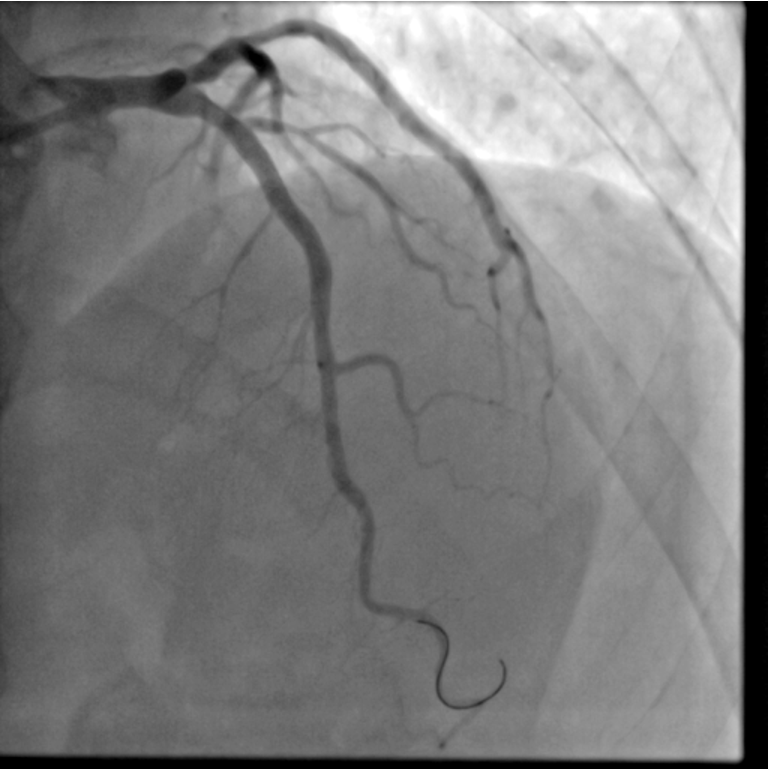

Our research interests are primarily focused on (but not limited to) Multimodal Reconstruction and Analysis of Digital Anatomy for Real-Time Clinical Interventions; in particular Segmentation, Landmark Detection, Tracking, Motion Modelling, Reconstruction, Registration, and Fusion of 2D/3D/3D+t Human Anatomical Structures (Cardiovascular, Cerebral, Biliary System, etc.) and Physiological information from Multi-Modality including X-ray, Angiography, MRI, CT, US, etc.

- Multimodal Reconstruction of Digital Heart for Cardiac Interventions in Real-Time.